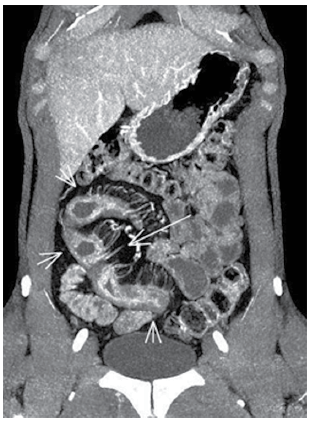

Dor abdominal constante e, às vezes, episódios de diarreia. Nesse caso, considerando-se a imagem a seguir, o diagnóstico mais provável é: